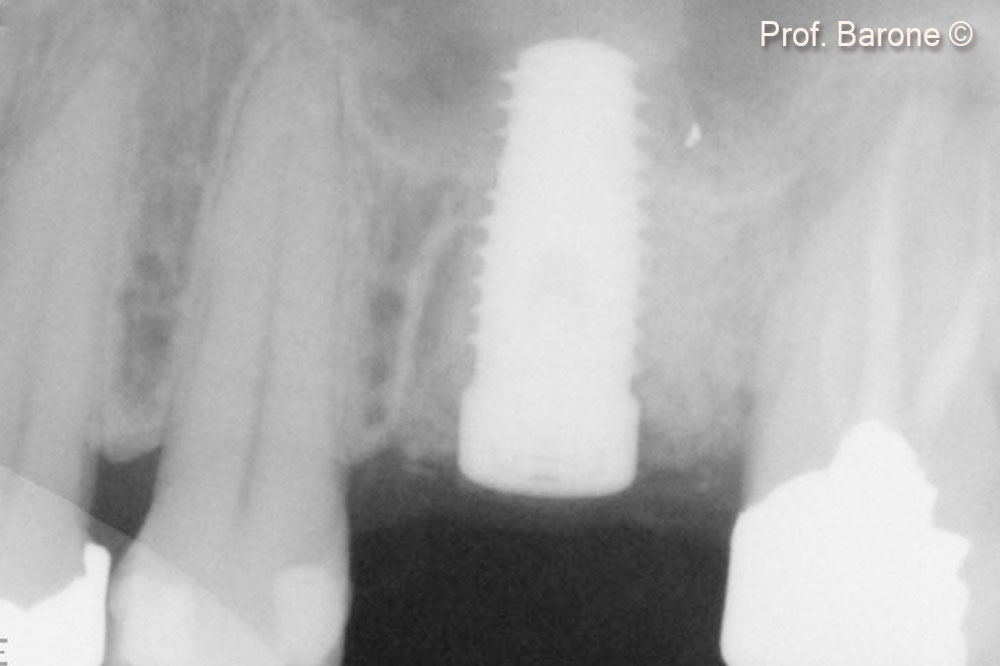

Periapical Radiograph immediately after implant placement